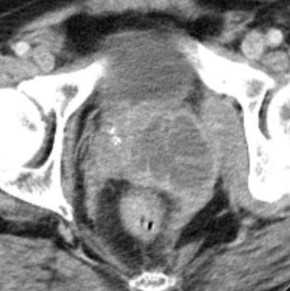

Увеличенные лимфатические узлы при раке простаты (указаны стрелкой)

КТ не является методом ранней диагностики РПЖ вследствие незначительной разницы в плотности опухолевой и неизмененной ткани органа. КТ-признаков РПЖ, за редким исключением не существует.

Показанием к использованию метода является:

— уточнение макроструктуры железы, при отсутствии дифференциации по данным УЗИ;

больших аденомах;

— Т3-Т4 стадия - для определения инвазии, распространенности процесса на окружающие органы и ткани;

— изучение наличия метастатического поражения регионарных лимфоузлов;

— уточнения характера изменений в костях;

— уточнения наличия отдаленных метастазов![Лучевая диагностика заболеваний предстательной железы]()

Рак ПЖ T4 (КТ)